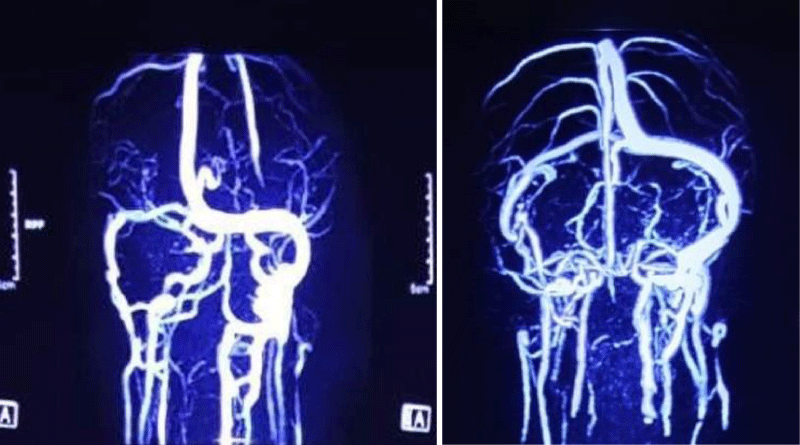

EMG showed increased insertional activities in the right sternocleidomastoid, abnormal spontaneous activities at rest, and reduced interferential patterns on maximal volition in the right trapezius muscles. However, there were no abnormal spontaneous activities at rest in the muscles of the tongue, face, cervical spine, and left upper extremity. He started treatment for aspiration pneumonia. Later, sputum culture revealed growth of Klebsiella pneumoniae sensitive to meropenem. Further workup revealed normal vasculitic screen (ANA, p-ANCA, c-ANCA) and normal CSF study. MRV of the brain revealed a thrombus in the right transverse sinus, the right sigmoid sinus extending up to the right internal jugular vein (Figures 2,3). D-dimer was raised 7. 71 mg/l (normal 0.5 mg/l). Thrombophilia screen was done. Protein C, homocysteine, lupus anti-coagulant, anti-cardiolipin antibody was negative, but protein S level came low (45%, normal 70% - 140%).

Download Image

Figure 3: MRV of brain showing thrombus in right transverse sinus, right sigmoid sinus extending up to right internal jugular vein.

So final diagnosis of jugular foramen syndrome (vernet syndrome) was made secondary to protein S deficiency. He was started anticoagulation with low molecular weight heparin, enoxaparin 60 mg subcutaneous twice daily bridging with oral dabigatran 150 mg twice daily. With treatment, patient became afebrile, cough reduced. He was kept on nasogastric feeding. On 11th day he was discharged with oral dabigatran and NG tube in situ. CRP and complete blood count came normal. On follow up at 2 months, he was stable, can take food orally but hoarse voice was persisting. Further follow up at 6 months, there was no evidence of bulbar palsy. His voice became normal and there was no nasal regurgitation or chocking while taking food. Follow up MRV was normal.